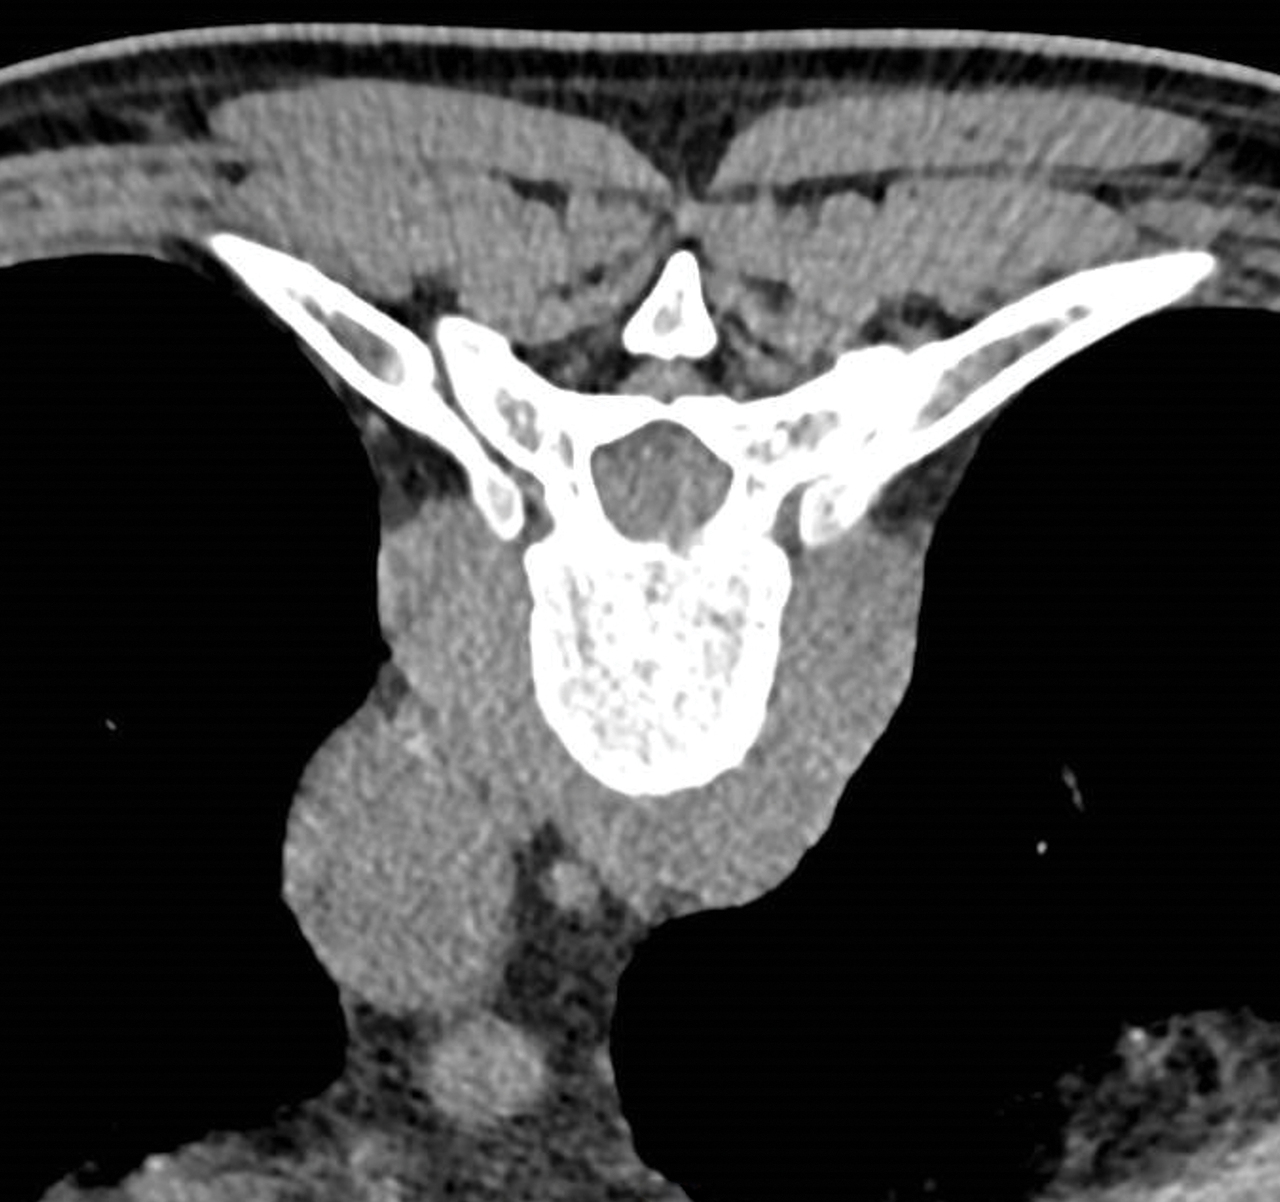

Homme de 74 ans, suivi pour une leucémie lymphoïde chronique, se plaignant de dorsalgies. Le scanner montre une masse paravertébrale de T9.

Quel est votre diagnostic